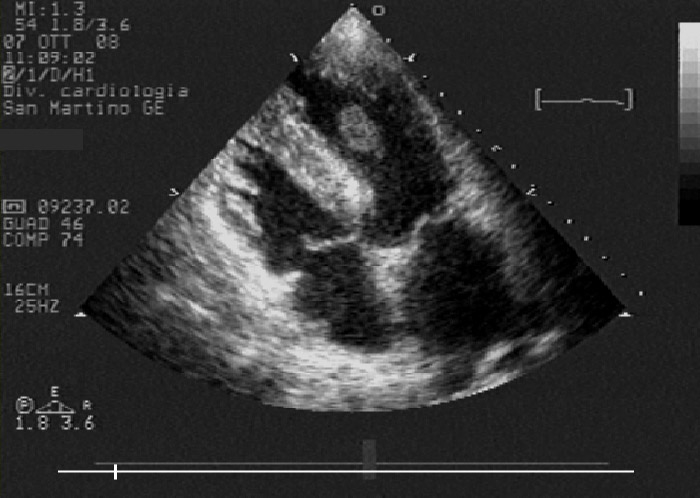

Figure 2

Echocardiographic modified four chambers view: note improvement of apical kinesis and floating, protruding left ventricle thrombus, whose morphology denotes a high risk of embolisation.

TTE after angiography revealed a protruding apical LVT. Heparin was continued and warfarin was added in the following days; target INR values were reached. TTE 96 hours after hospital admission showed a quite complete recovery in LV function and in regional wall motion; this situation probably promoted detachment of the apical LVT from the apical wall, so that the apical LVT assumed a floating morphology (fig. 2). On day six, the patient developed acute left arm ischaemia that fortunately required only medical therapy. At this time, TTE showed complete resolution of the apical LVT and complete recovery of LV ejection fraction.